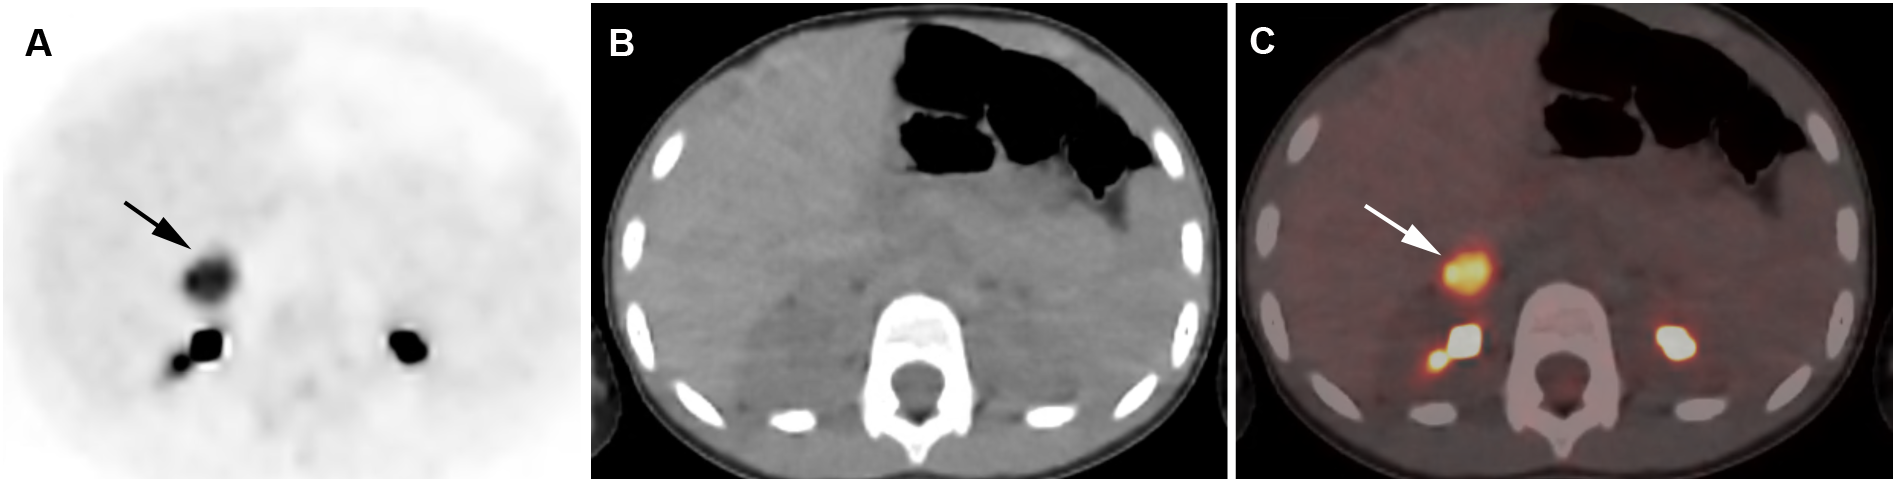

Figure 4

Adrenocortical adenoma. 5-year-old girl with history of neuroblastoma 4 years earlier. Suspected recurrence of neuroblastoma. Adrenal lesion noted on ultrasound as part of an evaluation of the urinary tract. [18F]FDG PET shows uptake in a right adrenal mass. Surgical resection of 2.5-cm adrenal adenoma. Transverse PET (A), CT (B), PET/CT fusion image (C). Intense [18F]FDG uptake in a right adrenal mass (arrows).